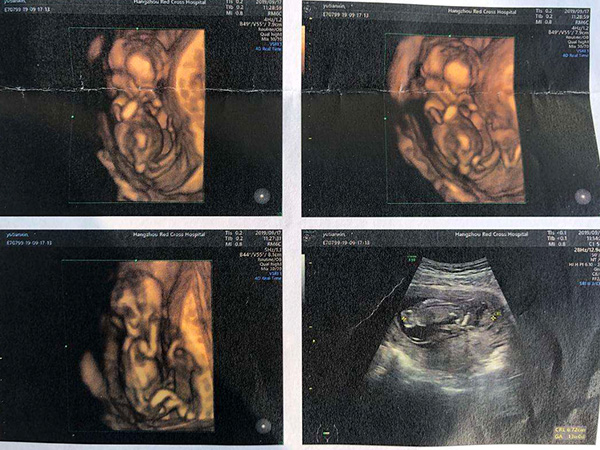

孕期很多爸爸妈妈们都想知道胎儿的性别,除了常规的b超检查单以及各种胎梦来推断胎儿性别之外,很多人都认为从nt检查时胎儿的姿势中就能看出是男孩还是女孩,一般认为如果是平躺的姿势就是女孩,是男孩的话通常都会弯曲着双腿,但实际上从nt检查看男女的方法远不止这一种,各位爸妈只要能找准诀窍,想提前知道胎儿的性别也不是很难。

nt检查本身是一项判断胎儿后颈透明带是否合格的孕期检查,实际上也是b超的一种,在这个过程中不可避免地就要对胎儿的整体情况进行扫视,虽然在孕前期胎儿的性别表现不是很清晰,但是生男生女还是有迹可循的。

在nt检查的过程中,常常可以通过胎儿的表现来确定胎儿的性别,比较常见的说法就是从胎儿的位置来进行判定,主要的依据就是通过男孩好动而女宝宝好静的特点来区分的,具体情况如下:

1.宝宝是平躺着的

这种情况下是女宝宝的可能性更大,因为相对于男孩来说,女宝宝就要文静的多,大多数情况下都是安安静静的躺在那里,所以如果医生告诉你宝宝在腹内是平躺着的,一般就是女孩。

2.宝宝是弯着的

宝宝弯着的又分为趴着、腿部弯曲以及侧躺等好几种情况,在排除意外情况的话,男宝宝的几率会更大,一方面是因为男宝宝天生就要活泼好动一些,另一方面也可能是男孩吸收的营养更多,所以需要通过运动来进行消耗。

不过凡事都有例外,在很多情况下,也可能表现出男孩是平躺而女孩弯曲的情况,这和个人的体质情况有很大的关系,所以通过nt检查中胎儿的姿势来判断男女具有一定的不准确性,对于其结果也要谨慎信任。

一般来说,从nt检查这一方面来确定生男生女并不可靠,更为准确的方法是通过四维彩超或绒穿,但这些方法都是不允许作为常规鉴定胎儿性别的,所以对于这些非科学判断男女的方法不可全信,当成参考即可。